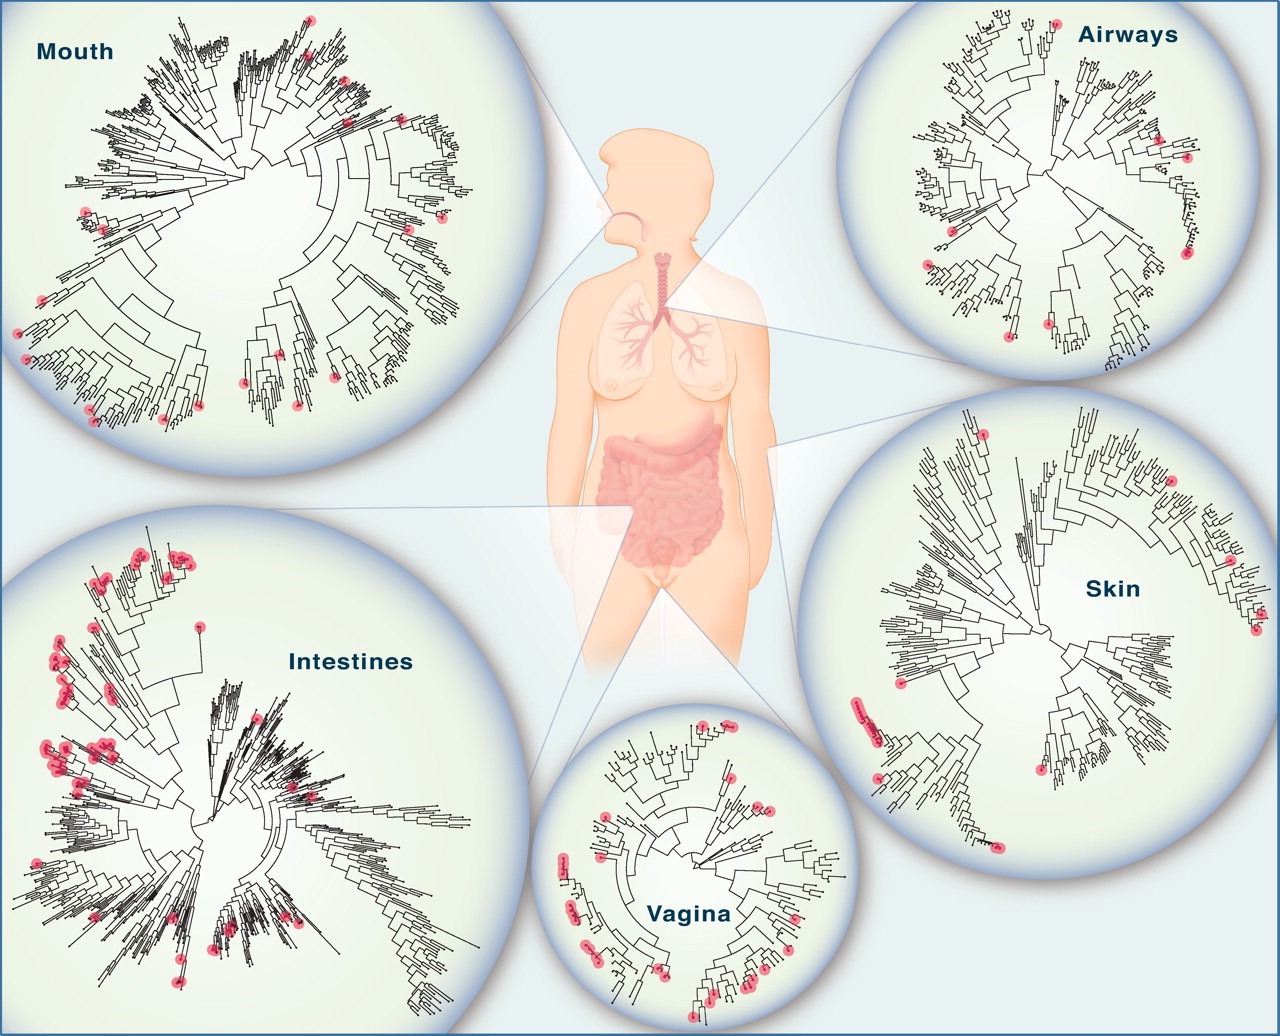

El Cuerpo Humano y su Universo Bacteriano. Fuente: ScienceMagazine